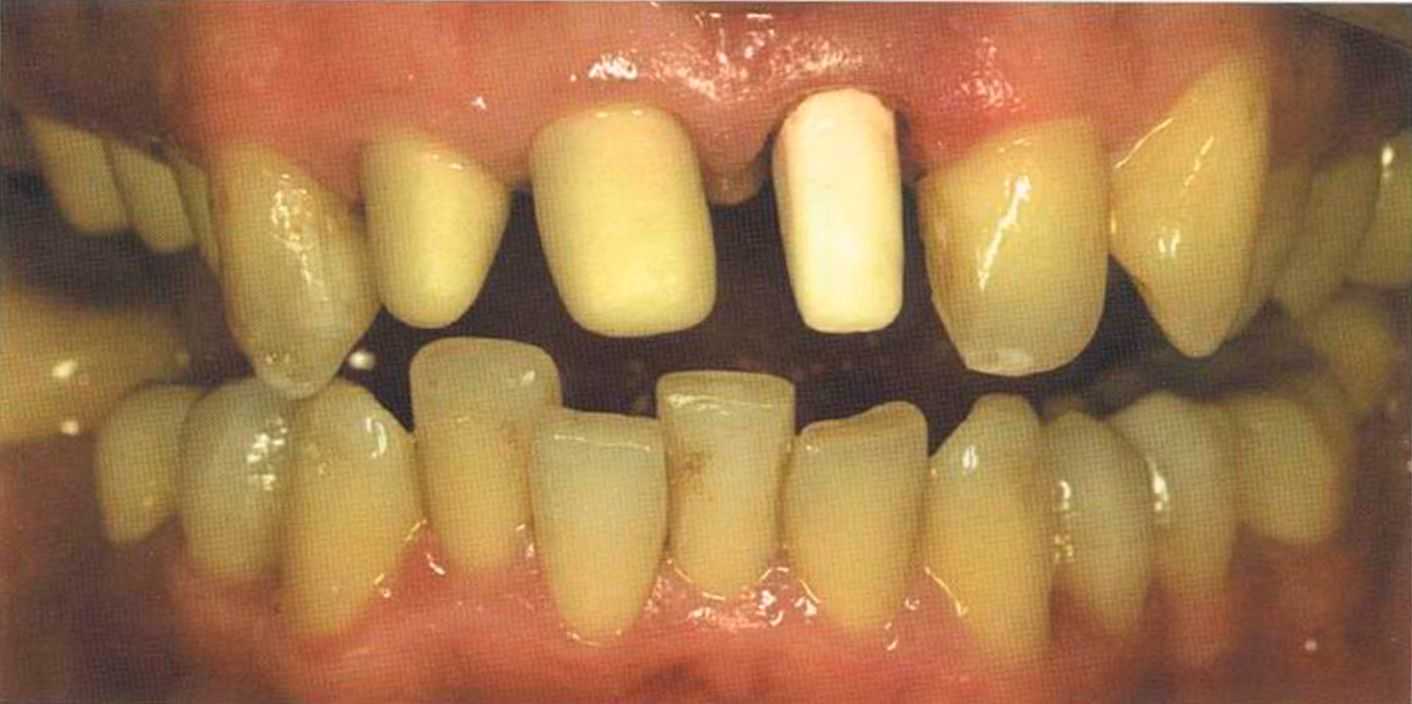

Эта женщина пришла в клинику доктора Лангханке с металлокерамической реставрацией.

Ей не нравились типичные в таких случаях темные края коронок и опаковость керамики.

Цвет 1М1 до 1М2 основной цвет в данном случае.

Отмечаем, что десна здоровая. Она гармонирует с коронкой ln-Сегат за счет отличных свойств материала

и отличного краевого прилегания.

Теперь коронки в области боковой группы зубов не нравятся, и в скором времени их тоже будем переделывать.

Коронки выполнялись в моей лаборатории вместе с пациентом. Мы работали долгих четыре часа, чтобы всем понравился результат. Обратите внимание на отражение света по краевым валикам. Мезиальные валики коронки 12 зуба гармонично переходят в дистальные валики 42 зуба. В идеальном варианте «отражающиеся валики» должны проходить по прямой линии. Это привило для всех мезиальных и дистальных валиков фронтальной группы зубов. Оно имеет очень важное значение и влияет на результат нашей работы.